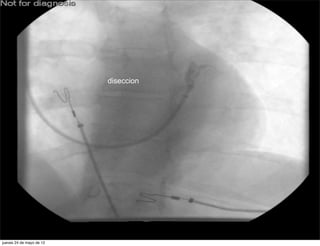

diseccion

ØComplicacion        si no usas las guias de

angioplastias.

ØComplicacion si no usas las guias de angioplastias. jueves 24 de mayo de 12